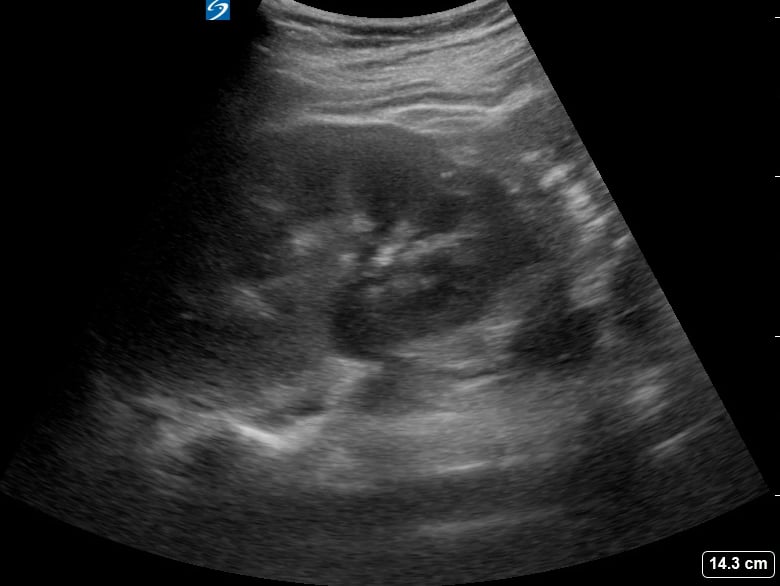

Hydronephrosis, in abdominal ultrasound, refers to the swelling of a kidney due to a buildup of urine. This occurs when there’s an obstruction in the urinary tract, preventing proper drainage. Common causes include kidney stones, tumors, or strictures, leading to dilation of the renal pelvis and calyces. Early detection via abdominal ultrasound is crucial to prevent irreversible kidney damage, as it provides non-invasive visualization of the urinary system and identifies the level of obstruction.

Medical ultrasound is essential for diagnosing hydronephrosis, offering real-time imaging that helps differentiate between various etiologies. Sonographers can assess the severity of kidney swelling, monitor progression, and guide interventions like stent placement. For accurate abdominal imaging, identifying hydronephrosis is key for timely management and preserving renal function, making it a critical aspect of diagnostic sonography.